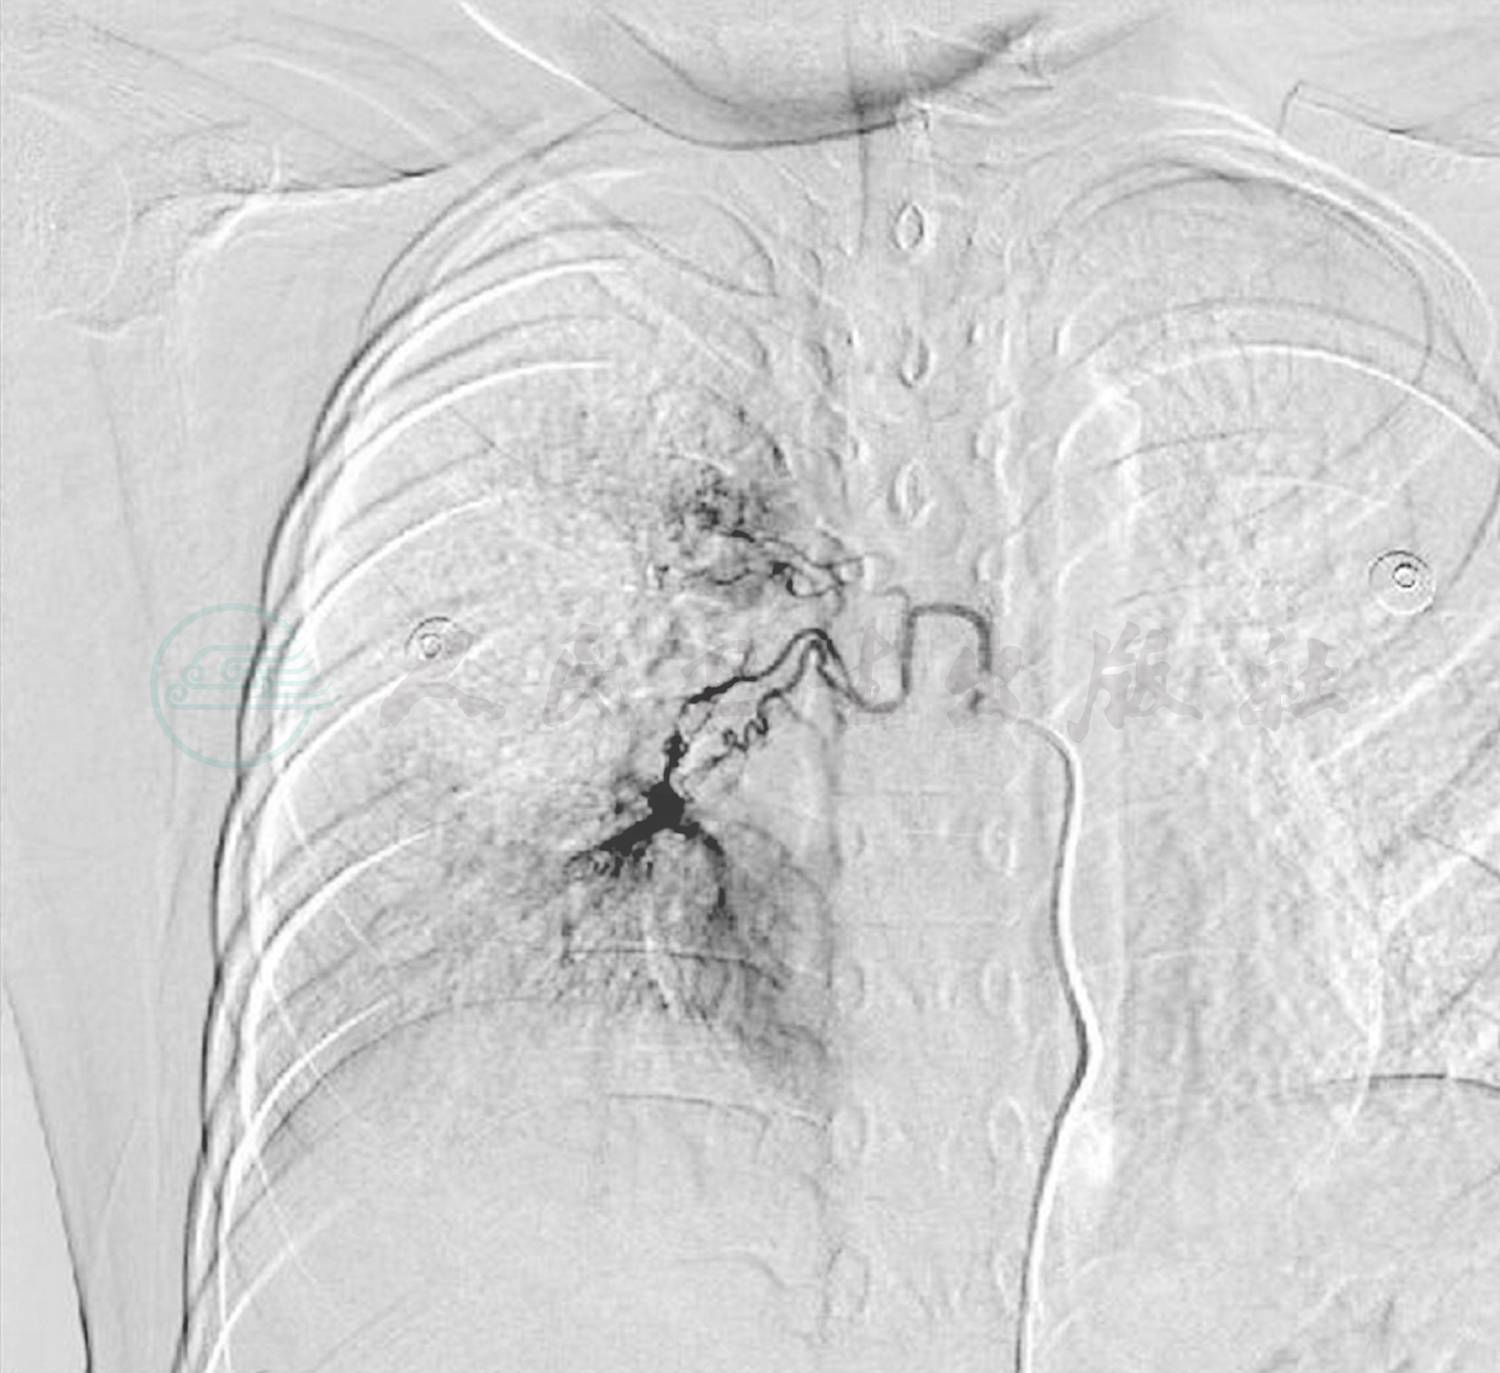

入院后急检血常规白细胞正常范围,予患儿头孢甲肟预防感染,同时完善病原学及相关常规检查。次日回报TB-Ab阴性;结核抗体阴性,肺炎衣原体抗体-IgM 阴性;肺炎支原体抗体-IgM 阴性,暂无结核、肺炎支原体及衣原体感染的证据;血红蛋白92g/L,提示轻度贫血。抗核抗体、抗nRNP抗体、抗Sm抗体、抗SS-A抗体、抗dsDNA抗体均阴性;抗线粒体抗体均为阴性;抗心磷脂抗体(ACA)、抗中性粒细胞胞质抗体测定(ANCA)及抗核抗体系列(ANA)均阴性,暂不支持系统性红斑狼疮等结缔组织病和ANCA相关性血管炎等引起的肺部损害。心电图正常,心脏超声正常不支持心源性咯血。入院第2天患儿再次咯血,量同前,检查血常规提示血红蛋白进行性下降提示肺部进行性出血,立即予患儿行支气管镜检查以明确出血部位,术中发现右肺下叶基底段可见鲜血涌出(图1),予1/10 000盐酸肾上腺素局部止血。因患儿出血量较大并急行肺部增强CT扫描提示:右肺中下叶见磨玻璃密度斑片影(图2),不除外肺血管异常导致出血,立即请介入科会诊,予患儿行支气管动脉造影术,术中发现血管略增粗扭曲,另见血管瘘(图3),予明胶海绵填塞后支气管动脉栓塞良好(图4)。夜间患儿再次出现呕血1次,约为50ml鲜血,患儿血氧饱和度下降,予患儿低流量吸氧,并予患儿垂体后叶素持续静脉滴注,联合凝血酶及酚磺乙胺止血并积极补液输血纠正贫血治疗。肺灌洗液结核菌涂片阴性,PPD阴性,结合支气管镜下的改变可除外肺结核;肺泡灌洗液未查到含铁血黄素细胞不支持肺含铁血黄素沉着症。患儿共住院治疗1周,无发热,未再次咯血及活动性出血表现出院观察。出院后电话随诊,患儿出院后无再次咯血,无反复感染及咳嗽史。

图3 支气管动脉造影示血管略增粗扭曲,另见血管瘘

诊断依据:①反复间断咯血病史;②发作时咯血量较大;③纤维支气管镜术中发现右肺下叶基底段可见鲜血涌出;④肺部增强CT扫描提示右肺中下叶见磨玻璃密度斑片影;⑤行支气管动脉造影术,术中发现血管略增粗扭曲,可见血管瘘。

支气管动脉瘘根据引流血管的回流方向不同,可分为3种类型:①支气管动脉-肺动脉 瘘(bronchial artery to pulmonary artery shunt,AAS);② 支 气 管 动脉 -肺静 脉瘘(bronchial artery to pulmonary vein shunt,AVS);③肋间动脉 -肺动(静)脉瘘(intercostal artery to pulmonary circulation shunt,IPCS)。根据造影表现,支气管动脉-肺动脉瘘分为4型:①肺动脉主干型:表现为增粗的支气管动脉发出分支,由其毛细血管与肺门或肺动脉主干沟通,肺动脉显示清晰,大面积肺实质染色;②肺动脉毛细血管型:表现为增粗的支气管动脉发出分支,由其毛细血管与肺动脉多支毛细血管交通,形成多个瘘口,呈现“瀑布”状;③枯枝型:表现为支气管动脉增粗不明显,肺动脉显示局限;④膈动脉型:表现为异常增粗的膈动脉分支毛细血管与肺底毛细血管沟通,延迟期可见肺动脉干或左心房显影。本例进行支气管动脉造影后,发现右下肺异常染色。远端呈现“瀑布”状,考虑属于肺动脉毛细血管型。